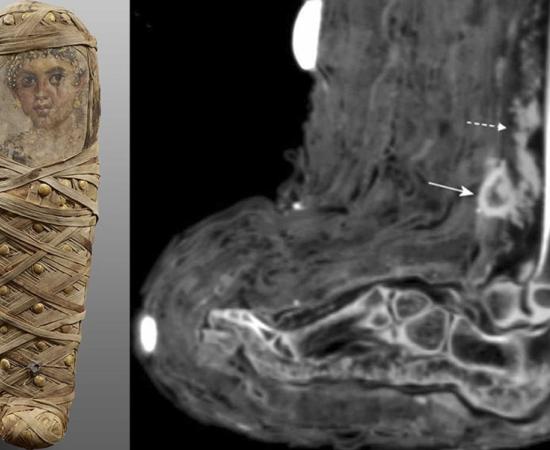

A new bioarchaeological study has identified what researchers describe as the first known case of deliberate mummification applied to a child sacrificed during the Inca capacocha ritual. The finding comes from CT scans of frozen child mummies recovered from the high Andes, and it suggests that in at least one case the body was modified after death, possibly transported, and even “repaired” in a symbolic sense. The research team, led by bioarchaeologist Dagmara Socha (University of Warsaw), used computed tomography to examine four naturally preserved child mummies from the Ampato and Sara Sara volcanoes in Peru, revealing injuries, disease indicators, and post-depositional damage that cannot be assessed reliably from surface inspection alone, reports PAP. Capacocha: Ritualized Child Sacrifice in the